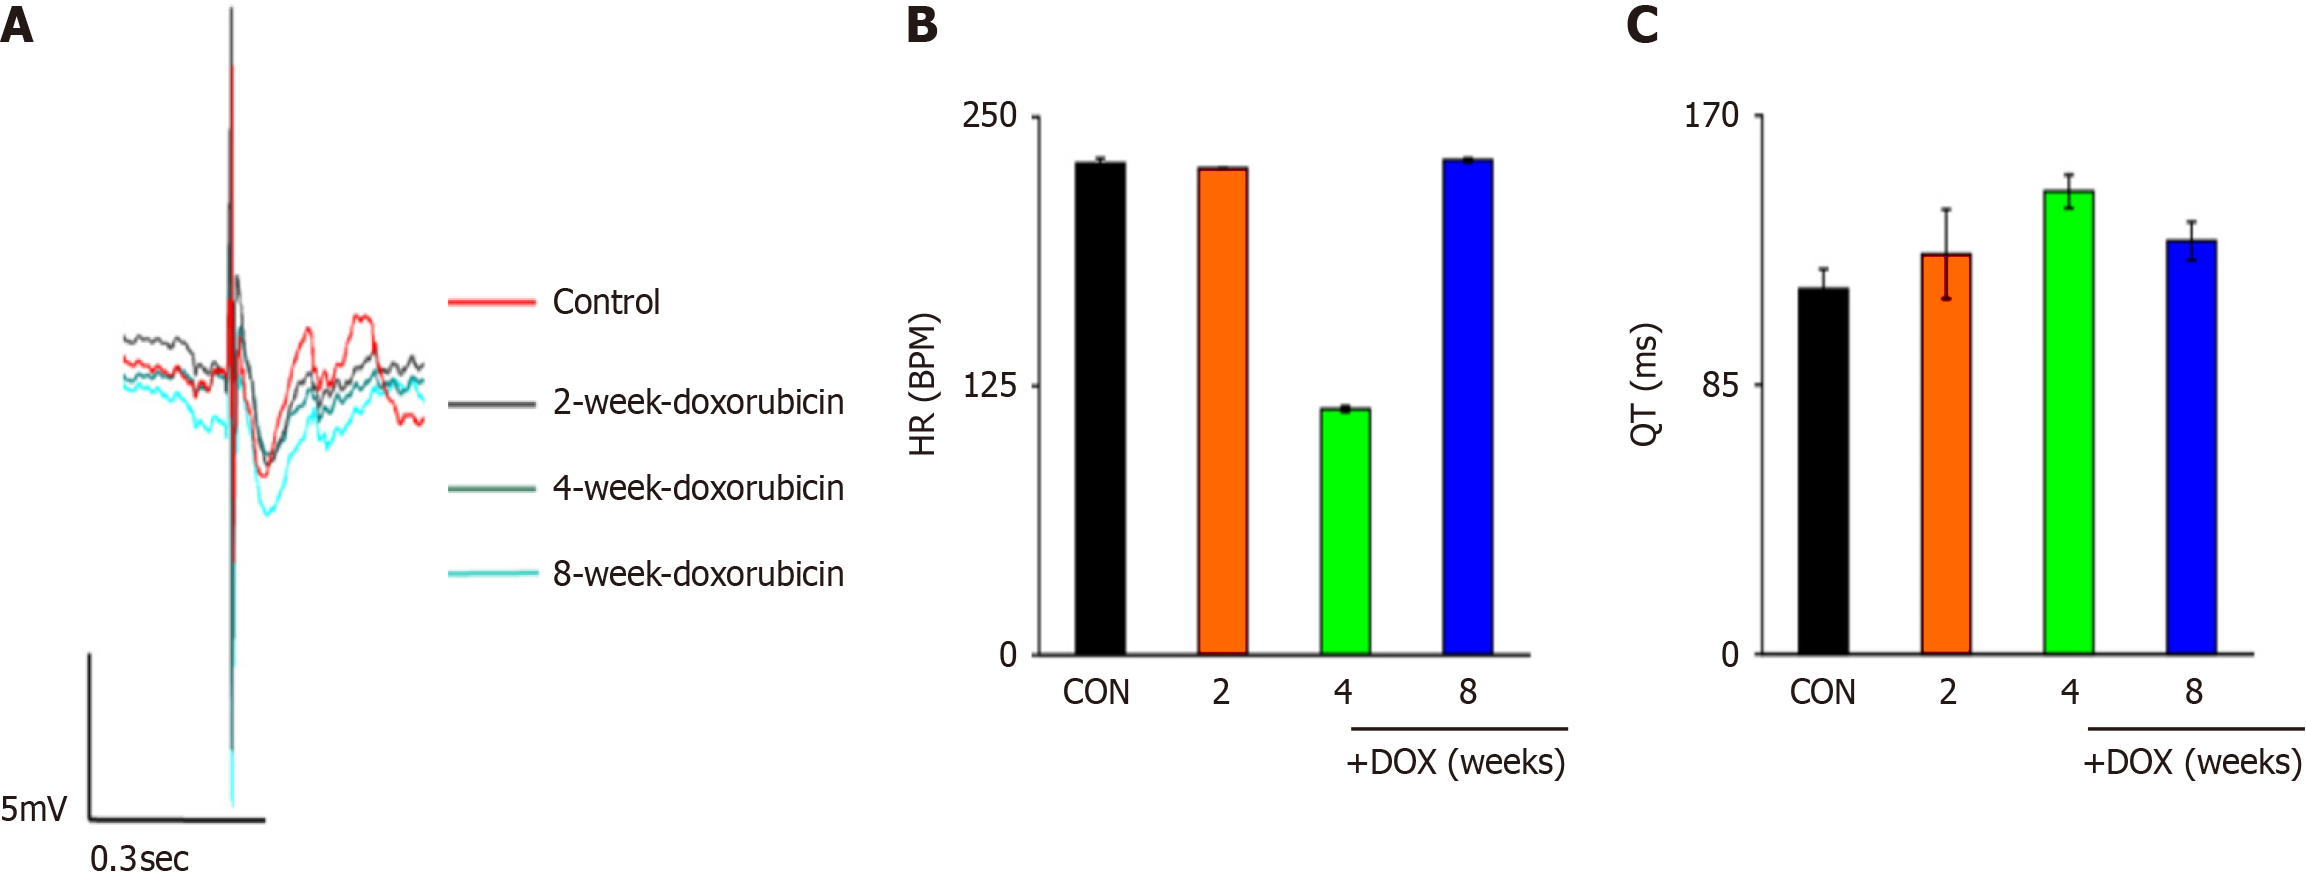

ECG is an important component of cardiac monitoring, and cardiac ECG changes were determined using multichannel electrophysiological labeling assays (Figure 3A). Heart rate slowed down after drug administration and all changes were significantly different (Figure 3B). Statistical analysis revealed prolongation of the QT interval (Figure 3C). When the QT interval was prolonged, the action potential timescale was abnormally prolonged, which may have led to increased Ca2+ inflow via L-type Ca2+ channels. Dysfunction of IK1 channels may have affected the function of other ion channels (e.g., IKr), which indirectly led to prolongation of the QT interval.